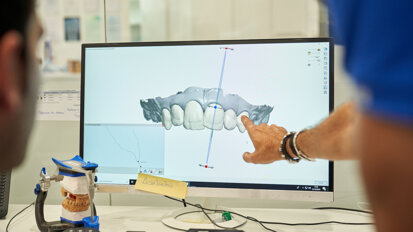

Ryc. 3 i 4_Przygotowanie rozległej powierzchni tkanki z użyciem rękojeści X-Runner i geometrycznego ustawienia prostokąta o aktywnym polu powierzchni 6 x 3 mm.